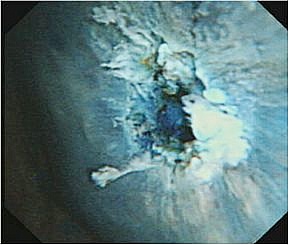

早期大腸がん、腫瘍を切らずに治す低侵襲な内視鏡治療

大腸における早期がんに対する内視鏡治療手技が発達し、根治ができる症例が増加して

おり、従来の治療に代わる新しい治療法として注目されていますが、当院では可能なか

ぎり食道、胃と同様に大腸における早期がんに対しては内視鏡的粘膜下層剥離術

(Endoscopic submucosal dissection、以下ESD)を行っております。

ESD治療の実際

治療手技は内視鏡治療用の電気のメスで直接,病変部を切って剥ぎ取る方法です。高度

な内視鏡治療技術が要求されます。比較的大きな病変も一括切除が可能であるため局所

再発率を下げることや、顕微鏡による正確な病理診断を行い、がんの悪性度を正確に調

べることができることなどのメリットがあります。低侵襲治療と正確な病理診断を兼ね

た非常に優れた内視鏡的治療になりますが、しかし正確な病期診断が不可欠であり、早

期がんに対する各種画像検査を行い治療の適応を決定します。